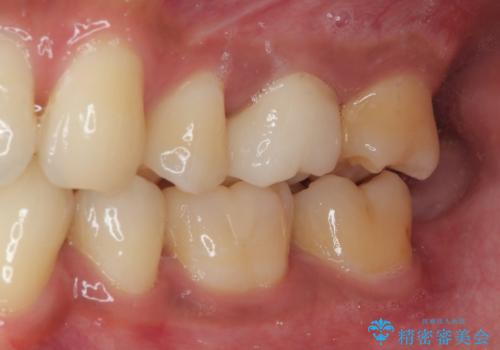

- セラミックにやり替えたいとのことで来院された患者様です。検査の結果、レントゲン上でメタルインレーの不適合を認めたのでセラミックインレーによる修復治療を行っていくことにしました。

拡大鏡視野下で、メタルインレー、虫歯の除去を行い、セラミックインレーに適した形に整えました。

見た目、機能面共に大変喜んでいただきました。

歯と歯の間の虫歯をコンポジットレジンや保険のメタルインレーで治すと段差ができたりして清掃性が悪くなり虫歯の再発リスクも上がるので、セラミックインレー修復やゴールドインレー修復などの適合の良い詰め物で治療することをオススメします。